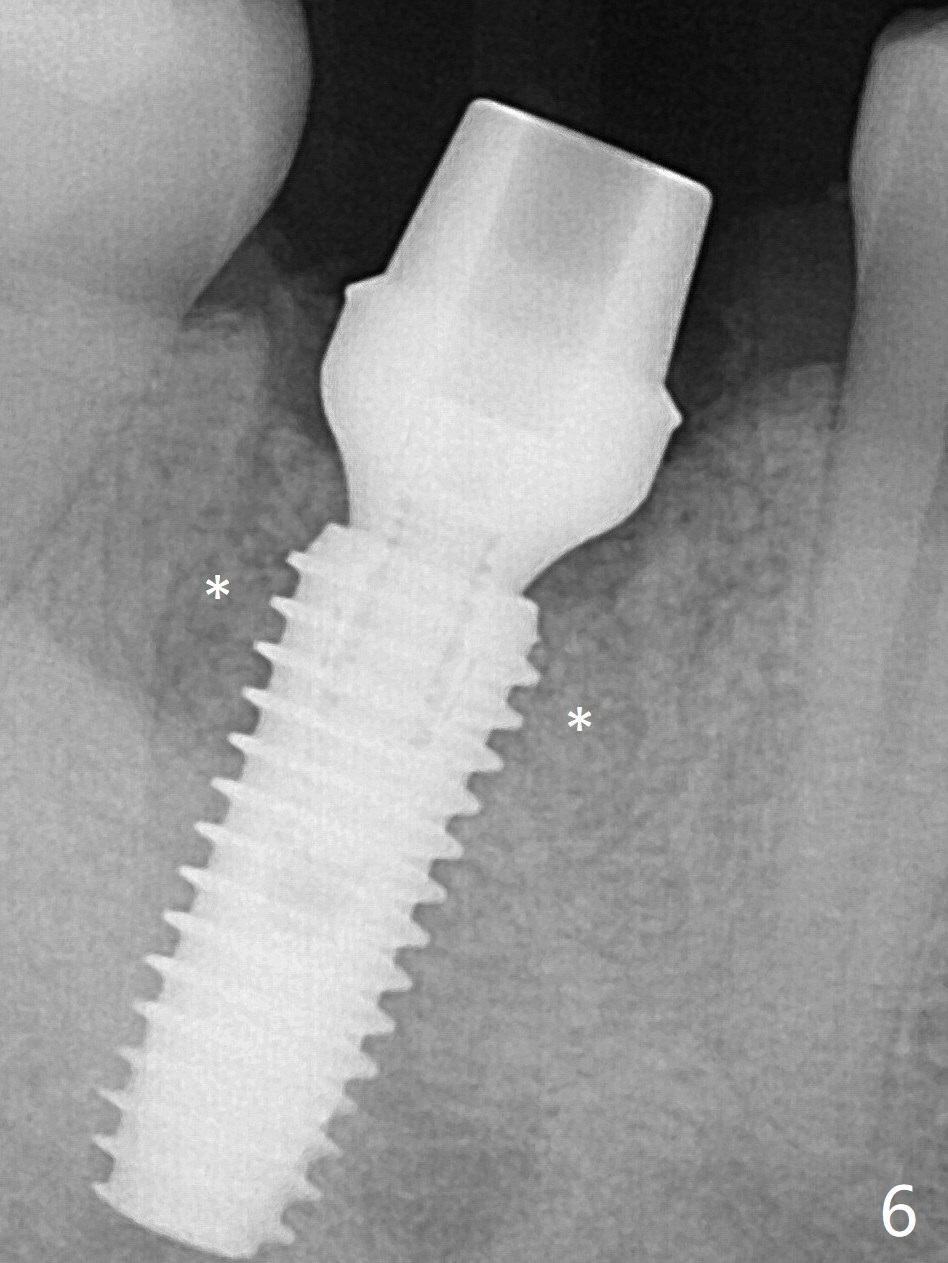

A 5x13 mm implant is placed superficially (Fig.5) with a trace of the previous osteotomy (yellow line) and deep space created by the mesial osteotomy (*). Red dashed line: the superior border of the Inferior Alveolar Canal. Apparently the pathological and iatrogenic defects are filled with allograft (Fig.6 *).